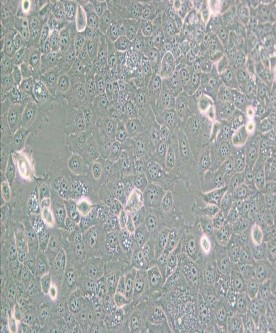

KYSE-30人食管鱗癌細胞

細胞形態 :上皮細胞樣,帶有長的偽足

生長特性 :貼壁細胞

完全培養基 :RPM I-1640(P M 150110)+H am's F-12(P M 150810)+2m M L-

Glu tamin e(P B 180420)+10% F B S(164210-50)+1% P /S(P B 180120)

培養環境 :空氣,95% ;CO2,5% 37℃

D erived from welldifferen tiatedin vasive esophagealsquam ouscellcarcinom a resected from middlein tra-th o racic esophaguso fa 64-year-old Japanesem an priorto treatm ent;cellline Established from tum orcells h etero tran splan tedinto athymicmice;d escribedin theliterature to be heterotransplan tablein athymicmiceand to carry p53 m utationandam plification ofcERB B,M YC and CYCLIN D1

倍增時間 :~ 20-30 hours

供體年齡 :女;64歲

組織來源 :食管鱗狀上皮

細胞類型 :腫瘤細胞

腫瘤類型 :食管癌細胞